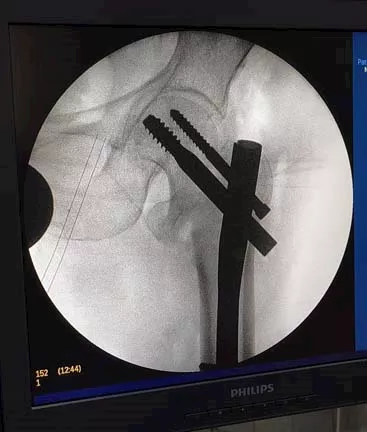

أعلنت مديرية الصحة بالدقهلية عن نجاح فريق طبي بمستشفى دكرنس العام في إجراء عمليتين جراحيتين معقدتين في العظام، باستخدام جهاز الأشعة التداخلي المتطور (C-ARM).

وأوضحت المديرية أن العمليتين شملتا تركيب كويرات بالرضفة اليسرى لمريض، وتركيب مسمار نخاعي في عظمة الفخذ لمريض آخر، مؤكدة أن الجراحتين تمتا بنجاح ودقة عالية.